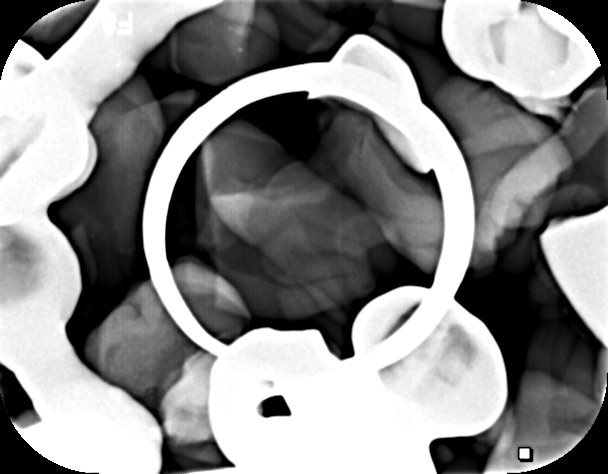

此次展出的作品的內容分為兩個部分,從微觀到宏觀的排列觀看的話可條列為:對物件自身的想像,以及物件與城市間的類比想像。〈無題〉(2017)與〈棄子〉(2017)系列是黃佳祥對牙齒這物件自身的考古想像,他藉由自身的專業,化身為牙齒的歷史考古者,以牙醫學的技術對牙齒進行考古歷史的研究,藉由切割、微距攝影及X光攝影,對牙齒進行個別物件的生命考究,並以此比喻個人。以〈無題〉為例,創作者將臼齒切開從中切開,露出雙牙根間的生命軌跡,齲齒、結石、抽神經與補牙在一個切面呈現,展現了牙齒本身的歷程,此外,切面的風景也陳述了牙齒主人自身與慾望的咀嚼歷史。

〈慾望之源〉系列(2017)、〈成人慾望〉系列(2017)、〈十萬比一的天際線〉(2017)、〈慾望深淵〉(2017)及〈祝你生日快樂〉(2018)則屬於物件與城市間的類比想像系列。藉齲齒的破敗深淵與城市的形成山巒城市地景的影像,暗喻人們慾望的堆疊與侵蝕。齲齒的形成對黃佳祥來說是慾望對自身的侵蝕,也是生命終究如此的破敗。而城市在作品裡坐落於微距攝影的齲齒中,被宛若群山的牙齒包圍,是牙齒在咀嚼生命慾望後所層疊的景象。〈十萬比一的天際線〉作品所寓意的就是城市與牙齒間的比例關係,〈祝你生日快樂〉(2018)中的五火或許是中醫象徵人類身體的五臟火,也或許僅僅是簡單轟然慾望的燃燒,但,以祝你生日為名,視覺上則反諷地以強烈的火焰意象呈現了慾望的叢生。〈慾望深淵〉以正俯視呈現俯觀紅塵的視覺角度,均質散佈於畫面的牙齒棄子宛若婆娑的諸眾,散落四方構成慾望都市。特別值得一提的是此次所展出的光柵技術,光柵科技除了以當代科技開啟了觀者視覺的奇幻性及呈現了影像的立體性外,重要的是在寓意上,光柵的視覺立體感呈現了台語成語「慾望滿天全金條,要抓沒半條」的意象,是心理、情感、精神與物質的真實與空幻交錯的虛無,慾望,無所不在卻捉摸不定。《咀》展,以實在之物論抽象的生命感悟,以物質的虛空論人生慾望的實在,咀嚼是黃佳祥眼中五色五味的入口,是人生來回不斷重複的慾望輪迴。